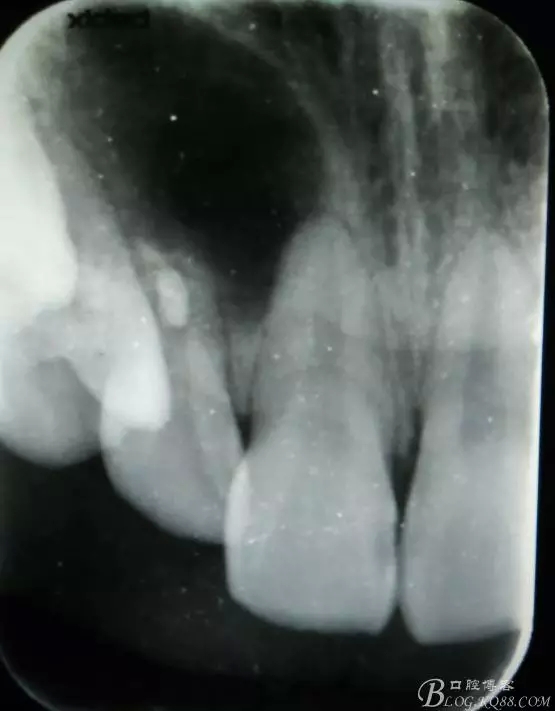

病例資料: 患者、柴xx、女、16歲。??茩z查及病歷如下圖: 患者同意我院正畸科建議,遂轉(zhuǎn)診倒外科。術(shù)前簽知情同意書。 治療過程: 圖1.術(shù)前的CBCT檢查:13阻生,疑為含牙囊腫??v剖面顯示12牙根吸收至根尖1/3。 圖2.局部麻醉下 。行唇側(cè)弧形切口,12松動(dòng)不到1°。 圖3.翻瓣、暴露骨面。 圖4.去骨、 暴露13牙冠 圖5.去骨、逐漸顯露13。 圖7.拔除13. 圖8.摘除囊壁 圖9.必須完整剝離囊壁。 圖10.摘除囊壁后形成的骨腔 圖11.超聲骨刀12根尖倒預(yù)備 圖13. 消毒棉球骨腔內(nèi)隔濕血液,紙尖干燥倒預(yù)備好的根管 圖14. 紙尖無血即可 圖15。MTA倒充填 圖16.骨腔填塞膠原蛋白海綿 圖17.拔除的13及摘除的囊壁 圖18.縫合 圖19.術(shù)后x線根尖片影像:MTA封閉根尖